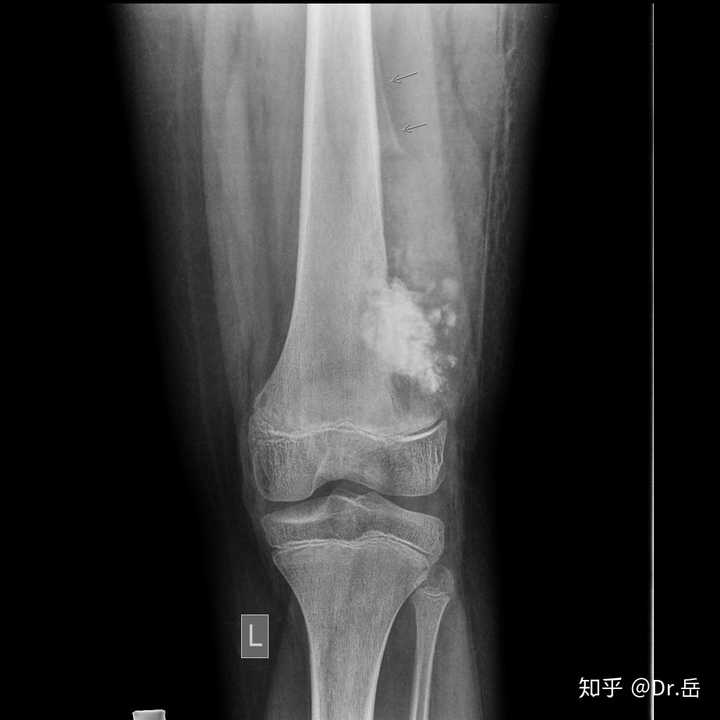

骨肿瘤x线图片,骨肉瘤x线图片

> 查看版本 肿瘤性骨样组织由胶原纤维和蛋白多糖组成,在肿瘤不同

骨肿瘤的x线表现

骨肉瘤x线图片

骨肿瘤x线

骨肉瘤x线